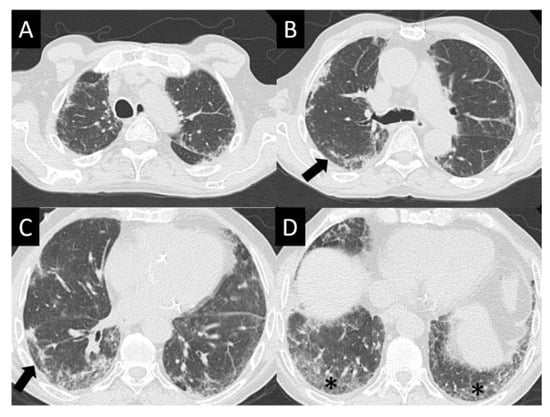

6.1.4. Chest Imaging

- Johkoh, T.; Lee, K.S.; Nishino, M.; Travis, W.D.; Ryu, J.H.; Lee, H.Y.; Ryerson, C.J.; Franquet, T.; Bankier, A.A.; Brown, K.K.; et al. Chest CT diagnosis and clinical management of drug-related pneumonitis in patients receiving molecular targeting agents and immune checkpoint inhibitors: A position paper from the Fleischner Society. Chest 2021, 159, 1107–1125. [Google Scholar] [CrossRef] [PubMed]